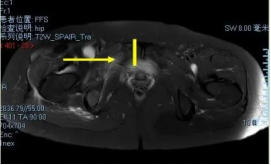

术前影像

穿刺活检提示骨盆软骨肉瘤

日前,安医大一附院骨病骨肿瘤外科胡勇教授团队成功完成一例复杂骨盆Ⅰ+Ⅱ+Ⅲ+Ⅳ区肿瘤切除与3D打印组配式半骨盆假体重建手术。患者为女性,53岁,下腰痛半年余,右侧臀部膨隆,右侧下肢轻度浮肿。右侧髂棘髂窝及臀部可触及巨大肿物,压痛明显,右髋外展前屈活动受限,右侧大腿感觉麻木,右足感觉运动正常。骨盆肿瘤切除重建是骨科专业中难度极大、风险极高的手术。骨盆肿瘤约占原发骨肿瘤的3%~4%,其中以软骨系统肿瘤最为多见,其次为骨巨细胞瘤、成骨肉瘤等,儿童尤文肉瘤亦好发于骨盆。